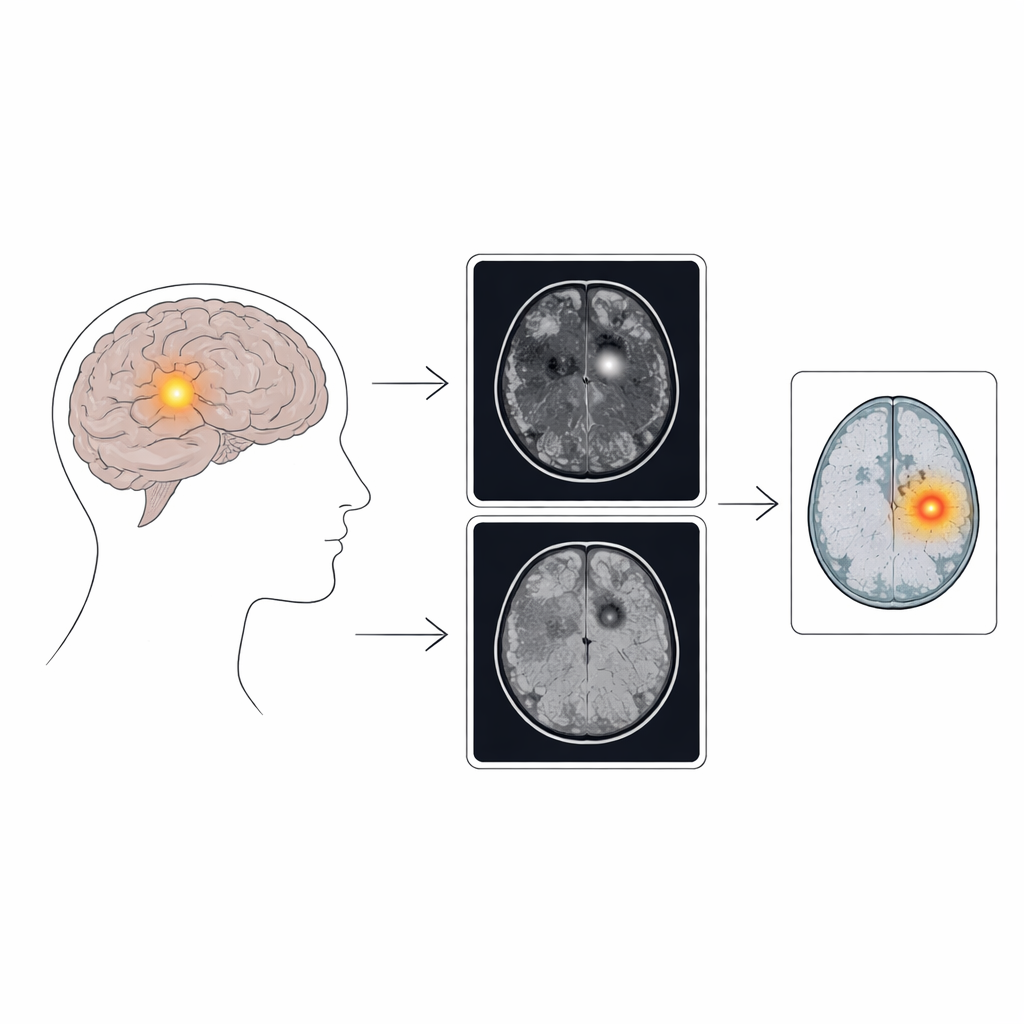

The core idea of the method is to generate a “pseudo-healthy” version of a patient’s brain scan and then measure how it differs from the real image. To do this, the team built on diffusion models, a powerful class of image generators that gradually add noise to an image and then learn how to reverse that process. In this work, the model is trained to convert one MRI type (a T1-weighted image, which highlights anatomy) into another type (a FLAIR image, which is especially sensitive to certain lesion features). During the reverse process, the model is gently pushed to transform suspicious regions so they resemble healthy tissue, while leaving normal areas essentially unchanged. The difference between the original FLAIR scan and the generated, “cleaned” FLAIR scan becomes an anomaly map that highlights likely lesion locations.

Different MRI sequences show focal cortical dysplasia in different ways. T1 images better reveal shape changes in the cortex, while FLAIR tends to make water-rich, abnormal tissue stand out with brighter signal and blurred boundaries. The authors exploit this complementarity by feeding the T1 image as a guide when generating the FLAIR image, encouraging the model to use structure from one modality and signal changes from the other. They also add a second source of guidance: a classifier trained to recognize which broad brain region (such as frontal or temporal lobe) contains the abnormality, or whether the scan is normal. This regional information steers the diffusion process to focus its “healing” efforts on areas where lesions are most likely, improving the chances of revealing small epileptic foci without heavily altering the whole brain.